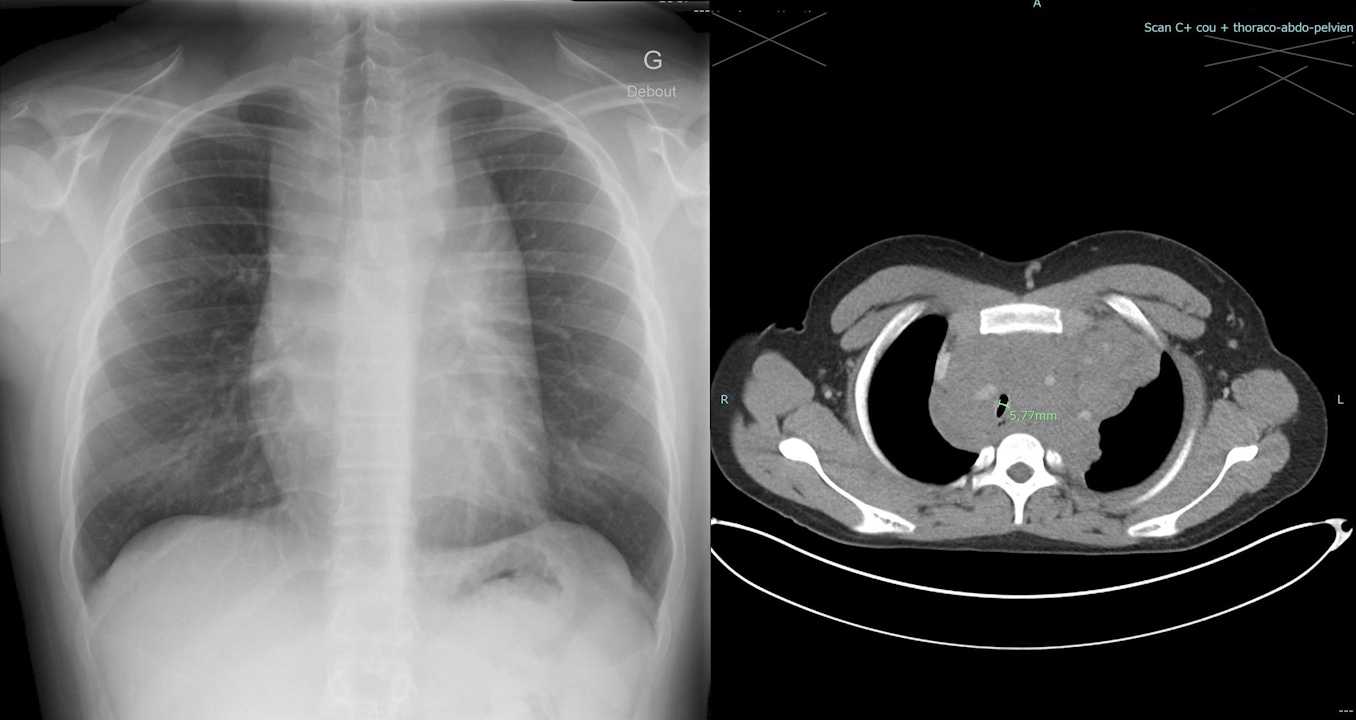

Пухлина в грудній клітині пацієнта на рентгенівському знімку (зліва) і комп'ютерній томографії (справа). Id Ali et al. / BMJ Case Reports, 2025

Підліток звернувся до лікарів зі скаргами на сухий кашель і скутість у грудях, які зберігалися протягом місяця, а також утруднення дихання в положенні лежачи, через що він був змушеним спати на двох подушках. Рентген і комп’ютерна томографія грудної клітки вказали на утворення в середостінні — просторі між легенями, згори обмеженому грудною клітиною, а знизу діафрагмою. Це утворення перетискало кровоносні судини, що живлять серце, бронхи та трахею.